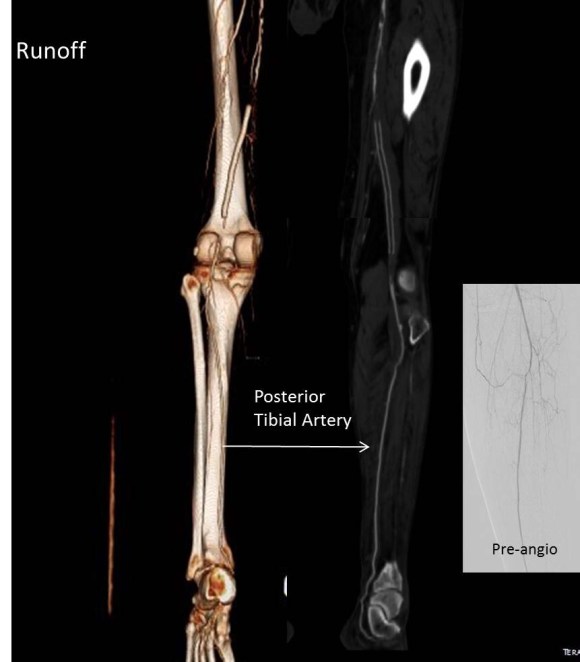

This patient was decided on amputation when our service was consulted, and after reviewing his CTA, I offered balloon angioplasty as his symptoms were primarily of paresthesia and neuropathic pain. I used cutting balloons and got angiographically satisfactory results.

It was only a month later when I heard the patient had returned with the same symptoms. He wasn’t angry nor full of any “I told you so” that frankly I was muttering to myself. Reviewing his CTA, he had restenosed to a pinhole. The vein, to use a scientific term, was “no good.”